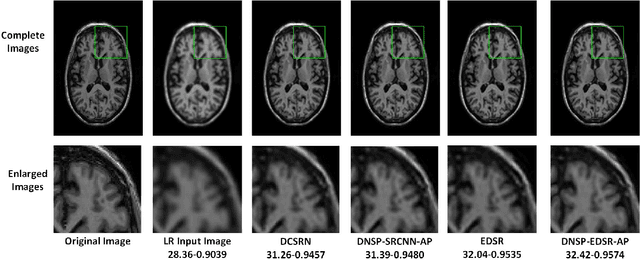

Abstract:High resolution Magnetic Resonance (MR) images are desired for accurate diagnostics. In practice, image resolution is restricted by factors like hardware and processing constraints. Recently, deep learning methods have been shown to produce compelling state-of-the-art results for image enhancement/super-resolution. Paying particular attention to desired hi-resolution MR image structure, we propose a new regularized network that exploits image priors, namely a low-rank structure and a sharpness prior to enhance deep MR image super-resolution (SR). Our contributions are then incorporating these priors in an analytically tractable fashion \color{black} as well as towards a novel prior guided network architecture that accomplishes the super-resolution task. This is particularly challenging for the low rank prior since the rank is not a differentiable function of the image matrix(and hence the network parameters), an issue we address by pursuing differentiable approximations of the rank. Sharpness is emphasized by the variance of the Laplacian which we show can be implemented by a fixed feedback layer at the output of the network. As a key extension, we modify the fixed feedback (Laplacian) layer by learning a new set of training data driven filters that are optimized for enhanced sharpness. Experiments performed on publicly available MR brain image databases and comparisons against existing state-of-the-art methods show that the proposed prior guided network offers significant practical gains in terms of improved SNR/image quality measures. Because our priors are on output images, the proposed method is versatile and can be combined with a wide variety of existing network architectures to further enhance their performance.

Abstract:High resolution magnetic resonance (MR) images are desired for accurate diagnostics. In practice, image resolution is restricted by factors like hardware, cost and processing constraints. Recently, deep learning methods have been shown to produce compelling state of the art results for image super-resolution. Paying particular attention to desired hi-resolution MR image structure, we propose a new regularized network that exploits image priors, namely a low-rank structure and a sharpness prior to enhance deep MR image superresolution. Our contributions are then incorporating these priors in an analytically tractable fashion in the learning of a convolutional neural network (CNN) that accomplishes the super-resolution task. This is particularly challenging for the low rank prior, since the rank is not a differentiable function of the image matrix (and hence the network parameters), an issue we address by pursuing differentiable approximations of the rank. Sharpness is emphasized by the variance of the Laplacian which we show can be implemented by a fixed {\em feedback} layer at the output of the network. Experiments performed on two publicly available MR brain image databases exhibit promising results particularly when training imagery is limited.